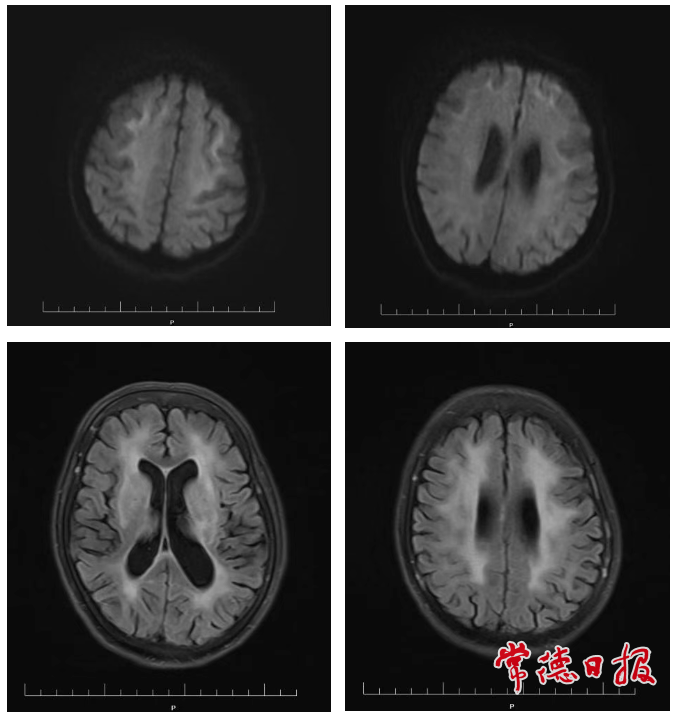

关键证据出现在次日完成的头部磁共振检查中:图像清晰显示患者脑白质存在典型的弯曲条带状异常信号,即诊断NIID高度特异性的“绸带征”。结合患者发作性脑病、进行性认知下降、瞳孔缩小等临床表现,NIID的诊断得以确立。